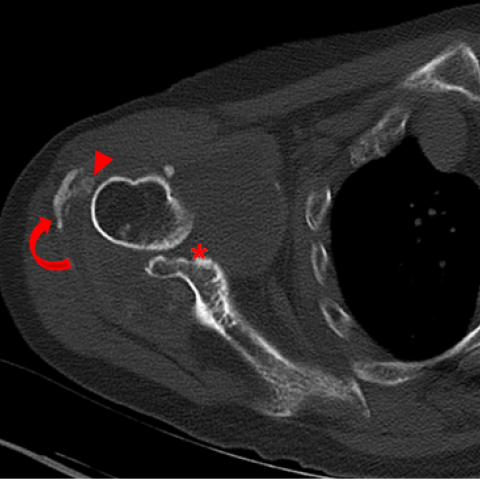

CT冠状面(a)和轴面(b)计算机断层扫描图像显示肱骨头和关节盂(*)有广泛破坏。肩峰下表面和锁骨外侧端也可见骨质溶骨性破坏(箭)。关节囊可见钙化(弯箭),关节内不规则钙沉积(箭头)存在。